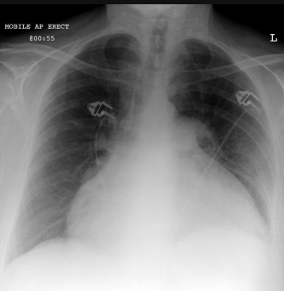

When looking at a CXR, we can use ABCDEF to look at each area of the CXR:

Trace the cardiac borders

Can you clearly see the left and right heart borders?

Can you see the descending aorta

Check the heart shadow for retrocardiac lung opacity

Check the diaphragm for overlying lung lesions in the posterior costophrenic recesses

Check the cardiac position

Is 1/3 to the right and 2/3 to the left?

Assess cardiac size

Is the cardiothoracic ratio < 50%?

Check the position and size of the aortic arch and pulmonary trunk

Check the width of the upper mediastinum

Look at the hilar vessels

Can you see them clearly on both sides?

Are they at a similar height?

Can you see a preserved hilar point bilaterally and a little higher on the left?

Heart

The heart must be assessed for its shape, size and location. Abnormal cardiac shift may reflect ipsilateral loss volume, lobar atelectasis or contralateral increase volume (large pneumothorax).

Enlargement of the cardiac silhouette may be due to cardiomegaly or pericardial effusion. When large, pericardial effusion may result in a 'water bottle heart' sign as shown below.